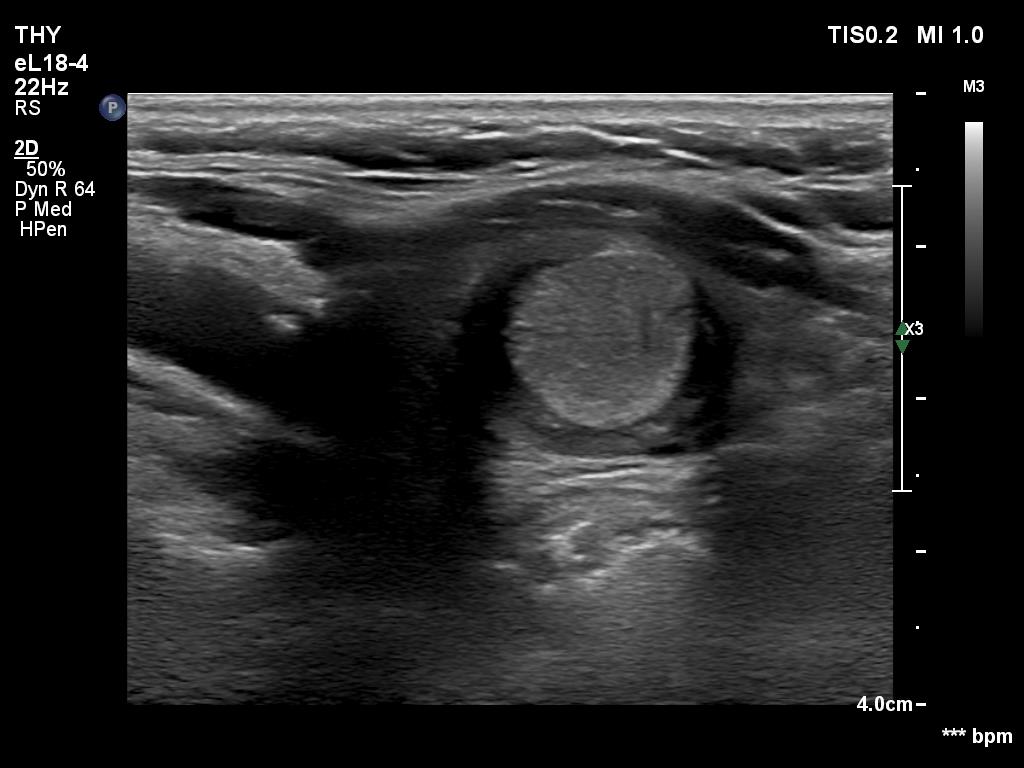

Clinical presentation: A 74-yr-old woman was referred for a follow-up examination. We last investigated her five years ago while the first occasion we met her was 23 years ago. At this first visit, a hyperechoic nodule was detected with the dimensions of 11x10x14 mm. Later, two times were aspirated 5 and 9.5 mL cystic content, from the nodule with a maximal diameter of 19 and 26 mm, respectively. Cytology was repeatedly benign.

Ultrasonography. The thyroid was minimally hypoechoic. The right lobe has several cystic areas, none of them corresponded to true nodules, these were dilated macrofollicles. There was a dominantly solid nodule in the right lobe. If we compared the echogenicity to a healthy thyroid, then the nodule should be regarded as echonormal, while if the reference tissue was the extranodular part of the lobe, then the nodule should be classified as hyperechoic. The nodule had bright echogenic granule. After a thorough analysis, the most likely explanation was that this was either a back wall figure or comet tail artifact. Nevertheless, microcalcification could not be fully excluded.

The discrete cystic lesions in the right lobe are not true nodules, therefore these should be classified as EU TIRADS 1 lesions.

The classification of the nodule in the left lobe depends on the interpretation of the bright hyperechoic granule. In my opinion, a single, equivocal bright granule should not be regarded as microcalcification when classifying a nodule. Therefore, I would categorize this nodule as an EU-TIRADS 3 lesion.